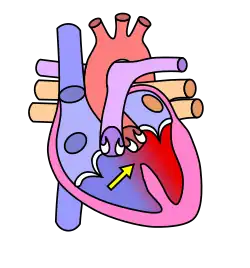

The cardiovascular system, in addition to needing to maintain itself within certain levels, plays a role in maintenance of other body systems by transporting hormones (heart secretes Atrial Natriuretic Peptide and Brain Natriuretic Peptide, or ANP and BNP, respectively) and nutrients (oxygen, EPO to bones, etc.), taking away waste products, and providing all living body cells with a fresh supply of oxygen and removing carbon dioxide. Homeostasis is disturbed if the cardiovascular or lymphatic systems are not functioning correctly. Our skin, bones, muscles, lungs, digestive tract, and nervous, endocrine, lymphatic, urinary and reproductive systems use the cardiovascular system as its "road" or "highway" as far as distribution of things such as nutrients, oxygen, waste products, hormones, drugs, etc. There are many risk factors for an unhealthy cardiovascular system. Some diseases associated are typically labeled "uncontrollable" or "controllable." The main uncontrollable risk factors are age, gender, and a family history of heart disease, especially at an early age.

The cardiovascular system also contains sensors to monitor blood pressure, called baroreceptors, that work by detecting how stretched a blood vessel is. This information is relayed to the Medulla Oblongata in the brain where action is taken to raise or lower blood pressure via the autonomic nervous system.